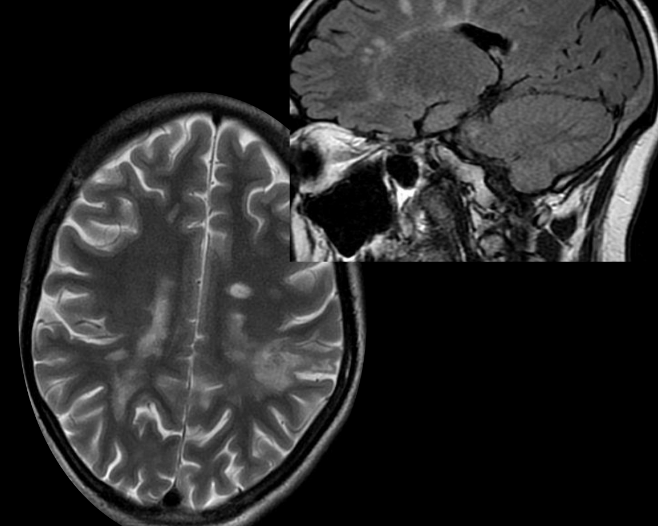

Imagen

RM

DEDOS DE DAWSON

HIPERINTENSIDADES CALLOSEPTALES EN T2 Y FLAIR